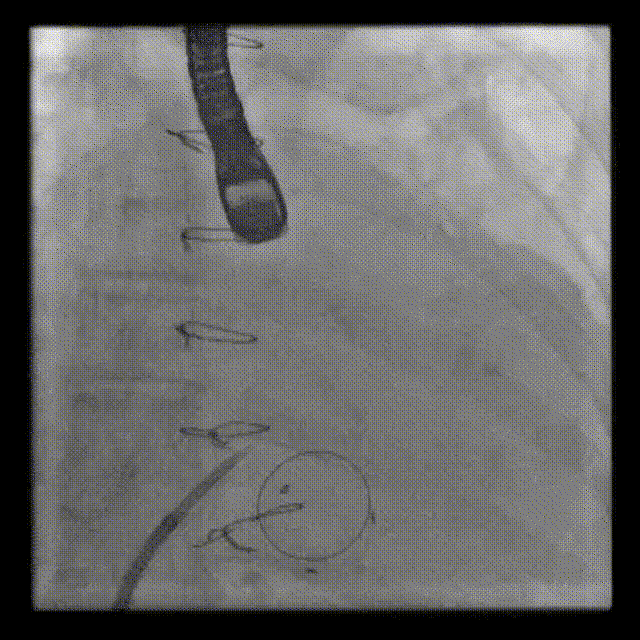

Positioning heigh: 90/10 preferred